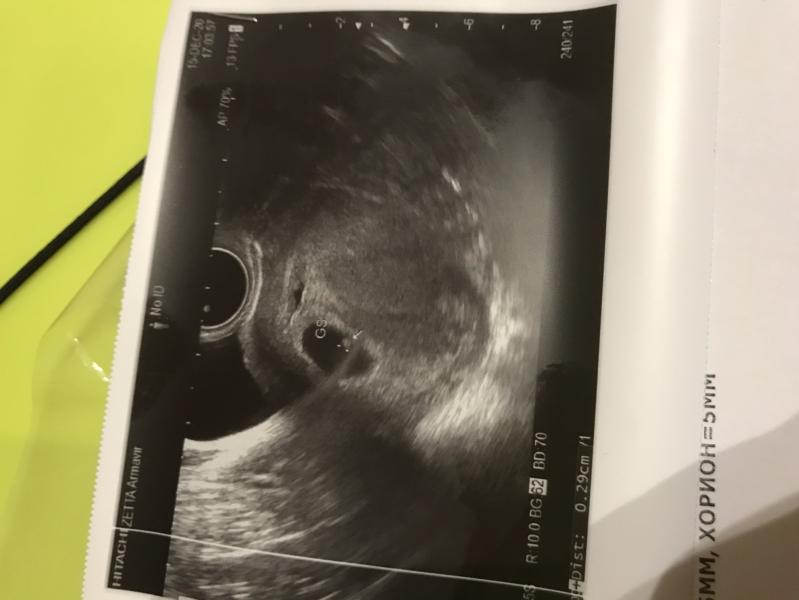

Сходила я на узи ребёночек один. Сердце ещё не прослушивается. Сказали угроза из-за тонуса надо пить больше витамин и покой. Я прям очень переживаю теперь так как у меня ноет живот постоянно. Завтра утром на приём к врачу все узнаю

@anna1896, врач сказала ещё тогда что как бы не двое что такой высокий

Мне она сказала что пока плохо прослушивается включала просто шум был 🧐